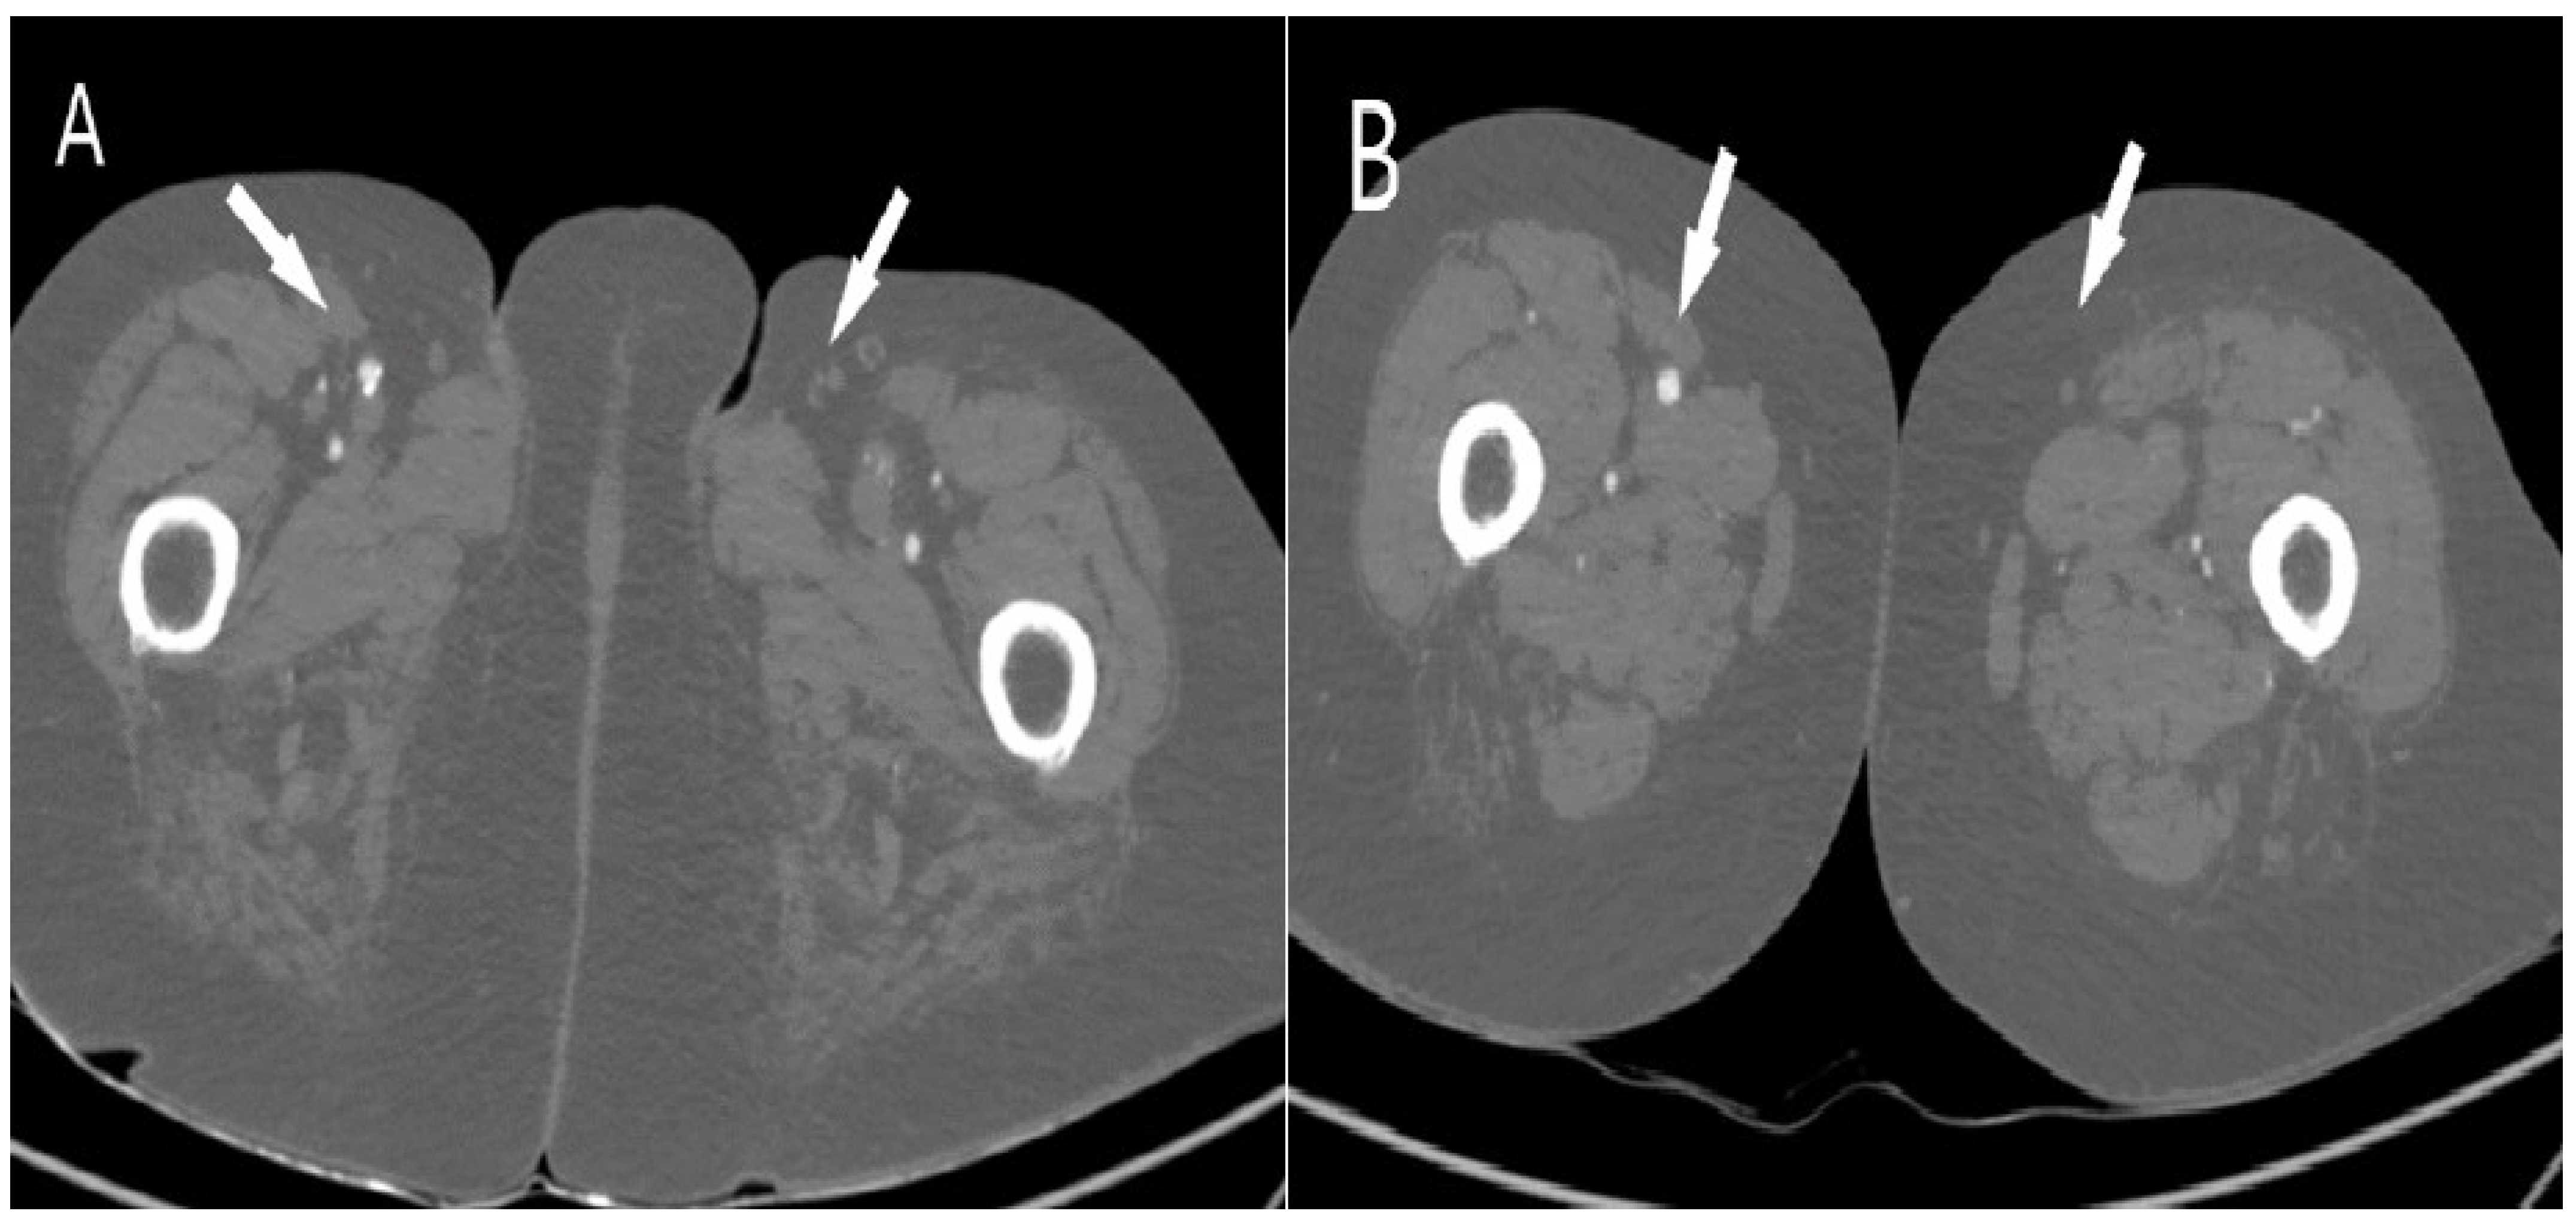

| All Patients | Patients with Pneumonia | Patients without Pneumonia | |

| n = 17 | n = 13 | n = 4 | |

| Patients with unilateral occlusions, n (%) | 1 (5.9) | 1 (5.9) | 0 |

| Patients with bilateral occlusions, n (%) | 16 (94.1) | 12 (70.6) | 4 (23.5) |

| Occlusions by stenosis degree, n (%) | |||

| Subocclusions | 126 (62.1) | 100 (49.3) | 26 (12.8) |

| Total occlusions (100%) | 77 (37.9) | 59 (29.1) | 18 (8.8) |